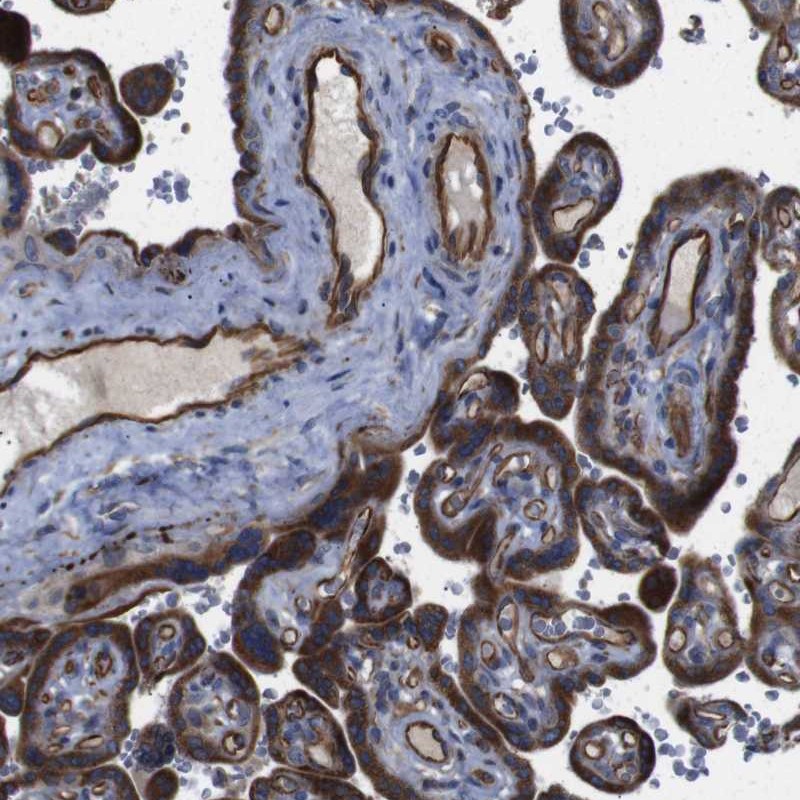

Immunohistochemical staining of human placenta shows strong cytoplasmic positivity in trophoblastic cells and endothelial cells.